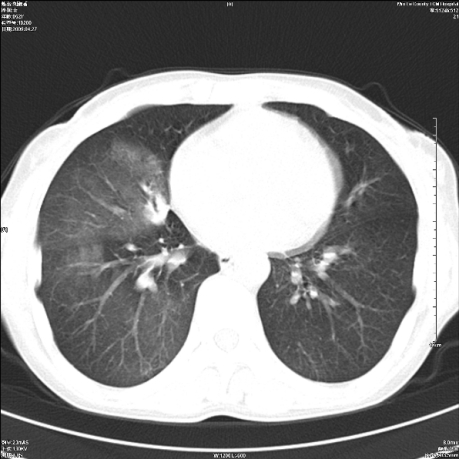

标题: CT19625:女52间断性喀血 [打印本页]

标题: CT19625:女52间断性喀血

考虑右肺下叶支气管病变,tb??

病灶内可见含气影。考虑右肺下叶内基底段炎症

考虑右肺中叶感染性病变并右肺中、下叶肺泡积血;建议抗炎、止血治疗后复查。

右肺中叶炎症;右肺中、下叶肺泡积血

右肺中叶支气管扩张并感染或咳血沉积,块右肺中下叶肺泡积血。

右肺中叶慢性炎症伴局部支扩并中下叶肺泡积血。

考虑右肺中叶感染性病变并右肺中、下叶肺泡积血。建议治疗后复查。